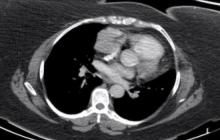

This video demonstrates a minimally invasive resection of a large thymoma in a morbidly obese patient. The utility of cardiac MR in operative planning, intra-thoracic CO2, angled cameras, and subxyphoid extraction are highlighted in this patient.